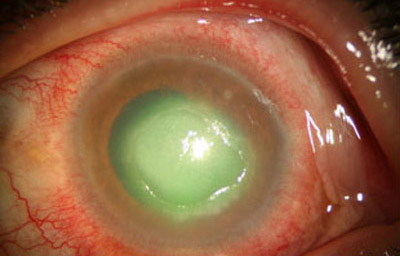

Superficie corneal irregular y grisácea, (Fig. 1, 2) con opácidades granulares en parche y formación de líneas epiteliales elevadas de aspecto granular (Fig. 3), que pueden arborizar dando imágenes de pseudodendritas. Opacidades superficiales satélites. (Figura 4) Inyección ciliar. Ulceración epitelial variante. (Figura 5).

Fig. 1 Síntomas de 15 días evolución

Fig. 2 Síntomas de 25 días evolución